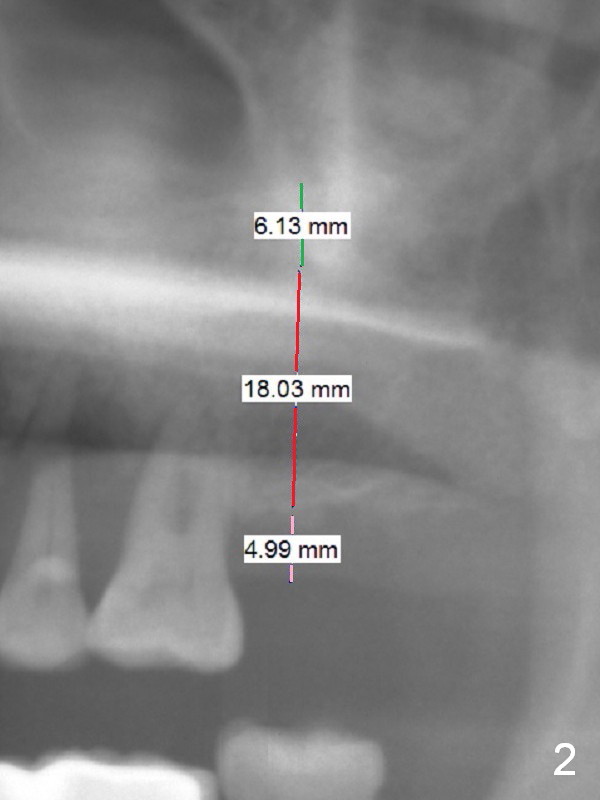

Long Implant and 5 mm Cuff of Abutment A 59-year-old man will return for #15 implant placement after the one at #13 (Fig.1). The bone allows an implant as long as 15-18 mm (Fig.1,2 red line). His gingiva is as thick as 5 mm, requiring an abutment with 5 mm cuff (Fig.2 pink line). The bone at #15 does not look dense or the ridge is narrow. Use #15 and DIO bone expansion kit for osteotomy. The less density of bone, the longer the implant. If a 4 mm abutment is long, adjust the opposing supraerupted tooth. Return to